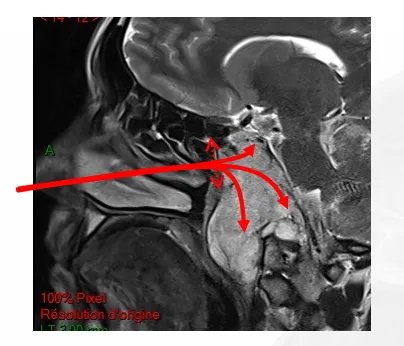

▼根据肿瘤的位置选择不同角度的一些角度镜图片

鼻腔末端是蝶窦,这扇门是蝶窦的前壁。在进入这扇门之前,不应该接触鼻腔内的任何组织。一旦进入蝶窦,可以往上、下、旁边不同方向进行手术操作。为什么呢?因为福教授有角度镜。

在通道很窄的手术中,需要使用有角度的弯曲的仪器,旋转可以从侧面深入到角落。福教授用30度、45度甚至70度(换数字)的内镜,目前他们也正在努力的开发这方面的器械。对于保护重要神经、更加准确移除肿瘤、灵活操作入路角度镜等都有重要作用。